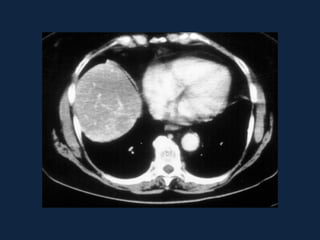

Hemangioma

 S/C              Fase art.

 Fase portal      Fase tardia